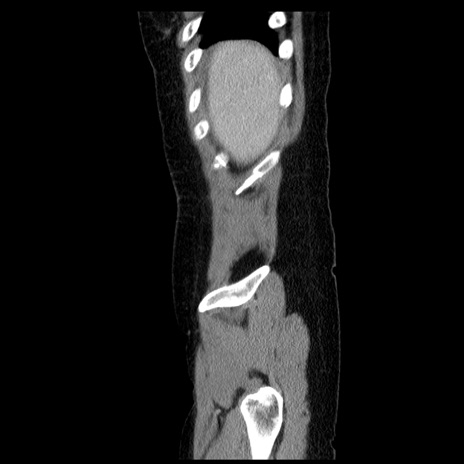

症例6(矢状断像)

冠状断像